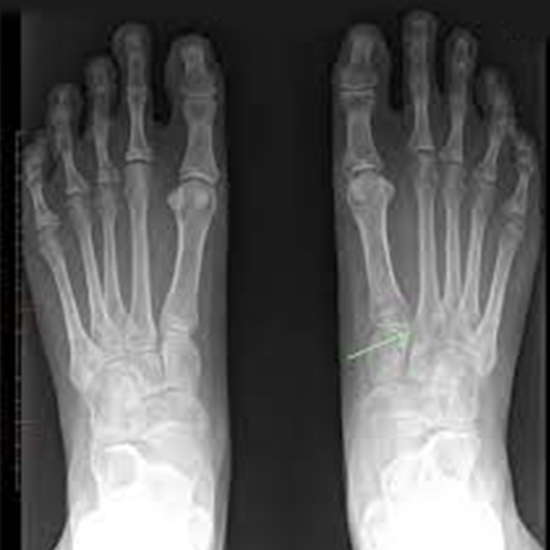

X-Ray Of Both Feet AP View (Weight Bearing) Procedure

Foot AP X-rays known as foot radiographs. The foot's AP x-ray is typically advised if the foot has suffered a catastrophic injury. To show how to perform while carrying weight, in weight bearing

This view is useful in assessing:

• Foot Trauma

• Bony tenderness at the base of the 5th metatarsal as well as at  the navicular bone

• Unable to lift more than four steps' worth of weight

• Non-traumatic foot pain

• To see varus –vulgus foot

• Foreign body

• Sprain

• Fracture